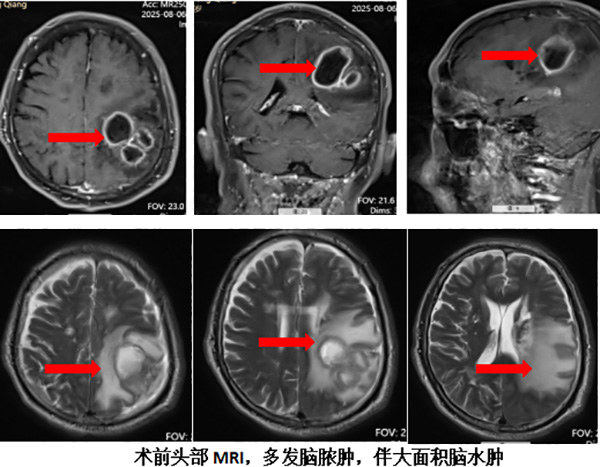

该名男性患者面部曾反复长出脓包,并有自行挤压的习惯。今年8月,他毫无预兆地出现右侧肢体无力、失语的症状,被紧急送入我院神经内科接受治疗。头部核磁共振检查提示其大脑左侧功能区存在一个“不简单”的病灶:核心是多发环形病灶,周围却被巨大的水肿带包裹,影像学表现高度怀疑颅内感染。

神经内科立即启动多学科会诊,神经外科行政副主任丁小明(主持工作)迅速到场。此时患者病情急剧恶化,伴有高热、肢体无力持续加重,并出现癫痫发作。丁小明结合影像与临床进程,果断判断为“大脑运动功能区脑脓肿”,且情况万分危急——脓肿为多房性,张力高,并临近侧脑室,病情快速进展的根源是脓液不断外溢,感染在播散,如脓肿向内破裂进入侧脑室系统,将引发致命的爆发性颅内感染,“这是一场遭遇战,制定正确策略后必须坚决执行,狭路相逢勇者胜,毫无退路可言 ”。